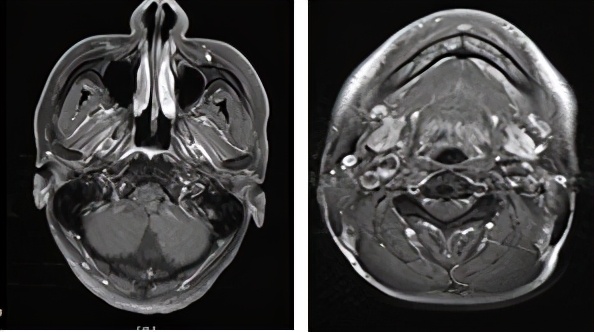

PD-1单抗联合化疗第一次影像评价(左:治疗前,右:治疗后2019.12)左颈部淋巴结稍有缩小